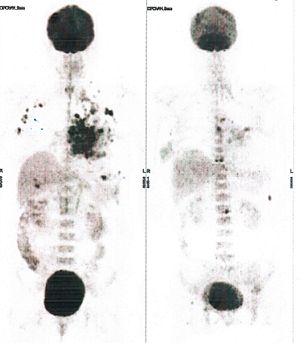

Below are some of the cases, from more than 80 cases we have treated so far with good results. When reading the PET/CT scans, the picture on the left is before treatment, and the picture on the right is after treatment. The intensity of black represents the activity of the cancer, but some black areas are not cancer: brain, heart, radioactive urine in bladder. For the heart, the intensity of black depends on the number of hours of fasting: if more than 10 hours, the heart is not even black, but if fasting is less than 6 hours, it is very black. The intensity of black in the brain can be variable in different scans depending on the brain activity at the time of the scan. The intensity of black in the radioactive urine can also be variable due to the hydration of patients and the time of injection of diuretic.

CASE NO: 1

(HEPATOCELLULAR CARCINOMA + STOMACH CANCER)

A middle-aged women who is very thin and very weak, can hardly walk, lying in bed most of the time. She saw a cancer specialist in a top hospital who discovered that she had massive hepatocellular carcinoma, and another cancer in the stomach. Given that hepatocellular carcinoma is incurable and stomach cancer is very difficult if not impossible to cure without surgery, she was told that nothing could be done for her. She came to ask us to help her. After just 4 treatment, the hepatocellular carcinoma went into remission, and the stomach cancer (arrow) became less active. Until today, more than 6 months later, the hepatocellular carcinoma is still in remission.

CASE NO: 1 - A FEW MONTHS LATER

A few months after successful treatment for hepatocellular carcinoma, and partially successful for stomach cancer, the PET/CT scan showed the stomach cancer becoming very active, with several metastases to the parts of the liver not previously involved by hepatocellular carcinoma. After a few treatment, all the active stomach cancer lesions in the stomach and in the liver went into remission.